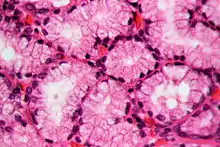

Histology

In staining during microscopic examination for diagnosis or research, acid dyes are used to color basic tissue proteins. In contrast, basic dyes are used to stain cell nuclei and some other acidic components of tissues.[8] Regarding cellular structures, acid dyes will stain acidophilic structures that have a net positive charge due to the fact that they have a negatively charged chromophore. Acidophilic structures include the cytoplasm, collagen and mitochondria. The two have an affinity for each other due to the conflicting charges.[9][10] Examples of acid dyes used in medicine include:[11]

- Lee's stain (stains reddish-pink).

- Phosphotungstic Acid Hematoxylin (PTAH) stain (stains blue).

- Eosin stain (stains pinkish-orange).